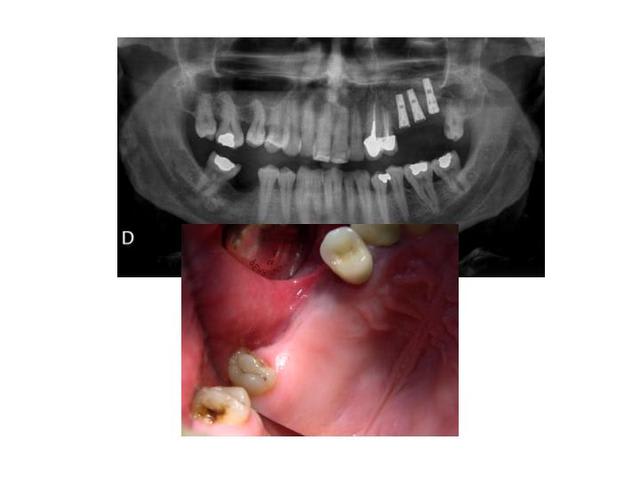

voilà, dans un droit de suite, la réalisation prothétique provisoire sur le cas présenté.

Diapositive2 kru9ce - Eugenol

Diapositive3 n4f4b7 - Eugenol

Diapositive4 psonwp - Eugenol

Diapositive5 yn7vz8 - Eugenol

Diapositive6 zssenm - Eugenol

As-tu une idée précise sur le degré d'intégration ? Je veux dire par là comment vérifies-tu que l'ostéo-intégration est plus grande entre le premier mois et le moment de la mise en charge ?

il faut attendre au moins 3mois et faire des control clinique et radiologique.